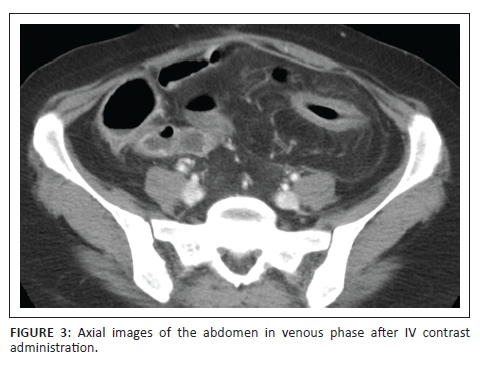

Five years prior to the current presentation, this 40 year old lady was diagnosed with Crohn's disease. She underwent multiple laporotomies for resection of strictured segments of small bowel and was placed on intensive disease modifying therapy including corticosteroids and immunosuppressive agents. Computerised tomography image in Figure 1 demonstrates inflammatory change of the ascending and descending colon with associated 'comb sign' of the respective right and left colic branches. Segmental small bowel and transverse colon wall thickening is noted. In Figure 2 there is marked mural thickening in the descending colon with a long segment stricture, 'comb sign' with hypertrophy of the paracolic vessels and associated fat stranding. Similar inflammatory changes are seen involving a distal small bowel loop in Figure 3. The computerised tomography study therefore demonstrated acute exacerbation with flare up of the bowel-related inflammation due to acute on chronic Crohn's enterocolitis.